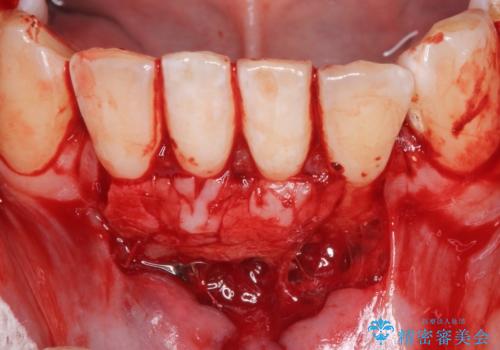

下顎前歯の歯肉退縮 結合組織を用いた根面被覆

- 歯肉退縮を主訴に来院された患者様です。

口蓋から結合組織を採取して、根面被覆を行いました。

十分な根面被覆を達成で患者様にも満足していただけました。